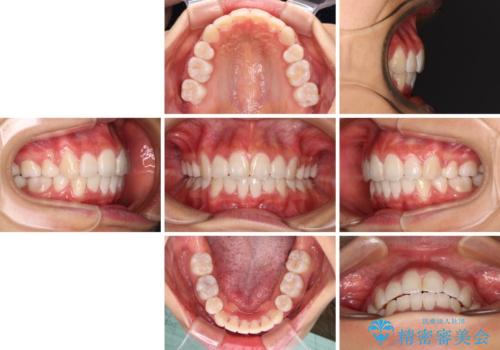

口元の突出感を改善 2年弱での抜歯矯正

- 1年7ヶ月

治療前の上下正中はずれていましたが、骨格的な上下左右差はあまり認められなかったため、正中を揃えて治療を終えることができました。

1年半ほどで治療を終えることができるとは我々も想像しておらず、患者様には大変満足していただきました。